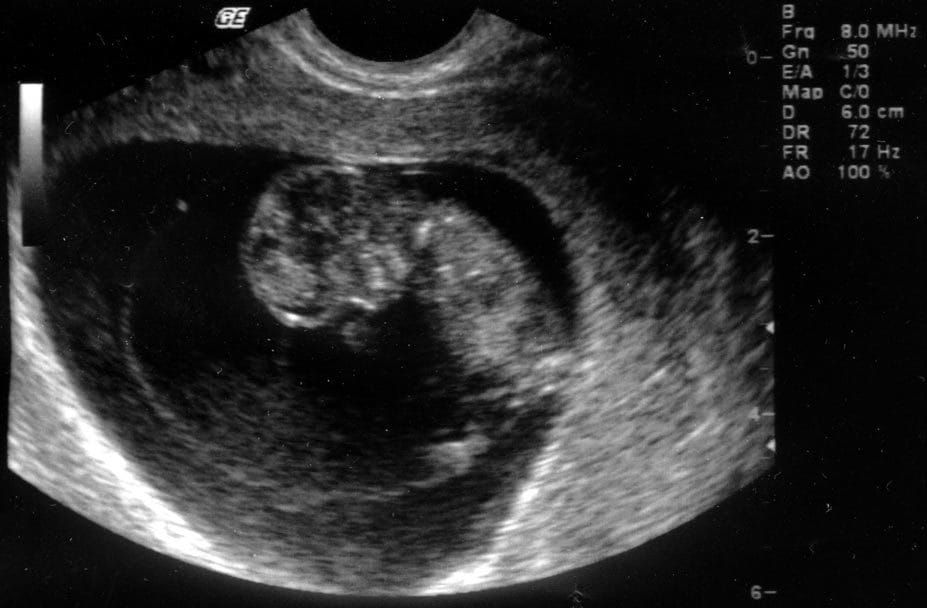

Researchers at Imperial College and the University of Warwick have identified molecular signals produced by cells in the womb saying whether an embryo can implant there or not, and suggest that drugs affecting these signals could be used to treat women vulnerable to miscarriages.

A fertilised embryo must embed itself in the uterus during a specific few days in the menstrual cycle for proper development. Previously,it was unclear how endometrial cells control the time during which they are receptive to embryos, and how they signal this receptiveness. A recent investigation into the chemicals produced by endometrial cells has found that a molecule called IL-33 is secreted during the receptive period, which regulates inflammatory and immune responses in nearby cells.

Usually, this molecule is secreted briefly, allowing embryo implantation only during the correct time in the menstrual cycle. However, the study found that in women who had suffered several miscarriages, IL-33 is secreted for up to 10 days, showing the endometrium is receptive even when it is not ready for embryo development.